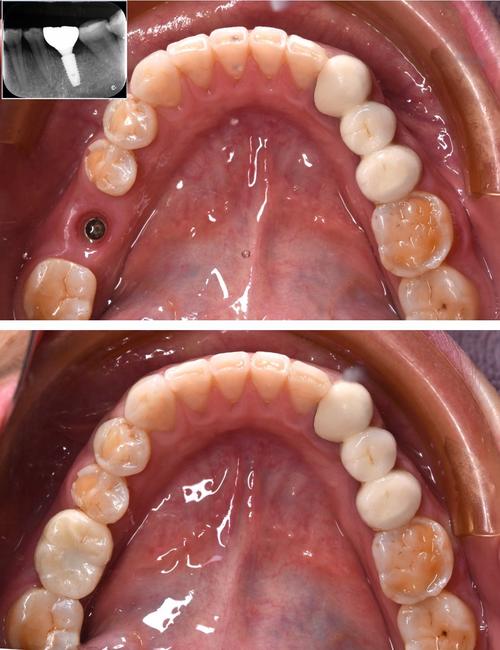

- 选择微创技术:如数字化导板种植、即刻种植等,能精准定位种植位置,减少手术创伤,术后恢复更快、疼痛更轻。